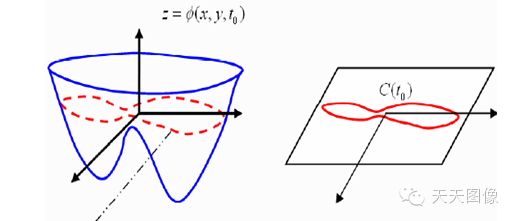

看下面的曲面,红色的虚线就是一条等高线。

图1

那么水平集算法的核心思想是什么嗯?那就是将要研究的问题,看做是更高一维空间的函数(也就是水平集函数)的零水平集。因此,当我们要追踪某一曲线(曲面)的演化过程,实际上就等价于追踪更高一维曲面的演化过程。

图2

如上图1至2的演化过程,如果对红色曲线建立一个随时间而变化的模型,是很困难的,因为发生了拓扑结构变化(一条曲线变成了两条),但是如果只是对蓝色的曲面建立随时间变化的过程,则是可行的,而红色曲线就是取其Z=0的水平集。